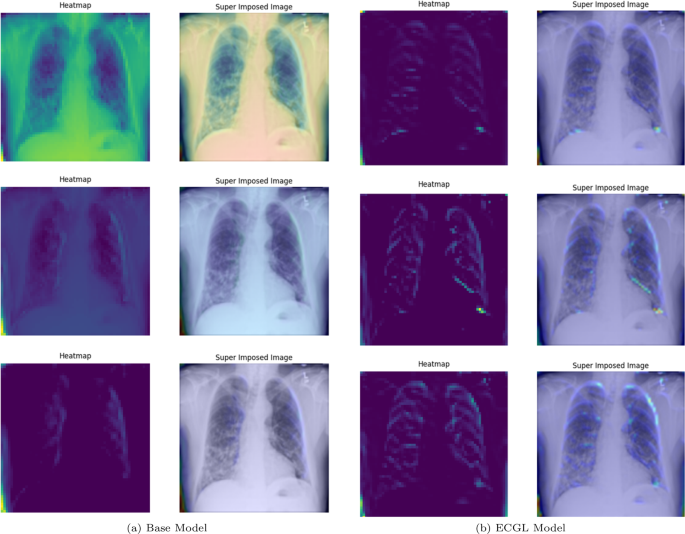

GradCAM Heatmaps and superimposed images of the (a) base model and (b) ECGL model for incorrectly labeled instances. The illustrated heatmaps correspond to GradCAM visualizations for labels 0 (normal), 1 (pneumonia present), and 2 (pneumonia absent, abnormalities exist), arranged from top to bottom, respectively. (a) base Model. (b) ECGL model

Likewise, Figs. 6 and 7 compare the proposed ECGL model and the Base model in terms of explainability by using GradCAM heatmaps. While both models generally seem to be focusing on similar areas (central region) of the chest X-rays, the color intensity in the heatmaps and superimposed images obtained from the ECGL model clearly shows a greater emphasis on certain regions that are related to the respiratory system and pneumonia disease. As it can be seen in Fig. 4(a) and 4(b) (correctly labeled instances), the highlighted regions of the Base model are more blurred, hazy, and spread out across the image, suggesting that the model’s decisions are less interpretable and apparent to the experts. Whereas the proposed ECGL model presents more focused and localized highlighted regions, showing that the model is primarily relying on specific areas of the image, relating to the particular region attacked by the disease, to make its prediction. The ECGL model makes it easier to understand the model’s reasoning and therefore presents more explainability. In addition, the ECGL model produces a more concentrated heatmap, indicating more confidence in prediction.

GradCAM Heatmaps (left column) and Superimposed images (right column) of the (a) Base model and (b) ECGL model for incorrectly labeled instances. The illustrated heatmaps correspond to GradCAM visualizations for labels 0 (normal), 1 (pneumonia present), and 2 (pneumonia absent, abnormalities exist), arranged from top to bottom, respectively

Moreover, in spite of both models’ similar performance illustrated in Fig. 5(a) and 5(b), the GradCAM visualizations clearly demonstrate noticeable differences. The Base model resulted in a more scattered visualization that may not correspond to the actual pathology. This indicates that the Base model’s prediction can be based on irrelevant features and not focused on the main required regions. The proposedECGL model, on the other hand, highlighted regions that are more relevant to the considered medical condition, suggesting that the constraints have helped the model focus on more meaningful features.

Unlike the Based model, the ECGL model’s heatmap for the incorrect prediction is more localized, highlighting a specific region in the lung. The overlay shows that there is indeed an abnormality in this area, but it could have been insufficient to confidently classify the image, which resulted in an incorrect final prediction. While such false predictions highlight the complexity of the task, the findings suggest that adding the constraints and guiding the model with domain-specific explanations through proposed ECGL can enhance the model’s explainability even when overall accuracy remains quite the same. Using such explainability, the experts can better identify the model’s deficiencies and limitations, leading to efficient mitigation of them.